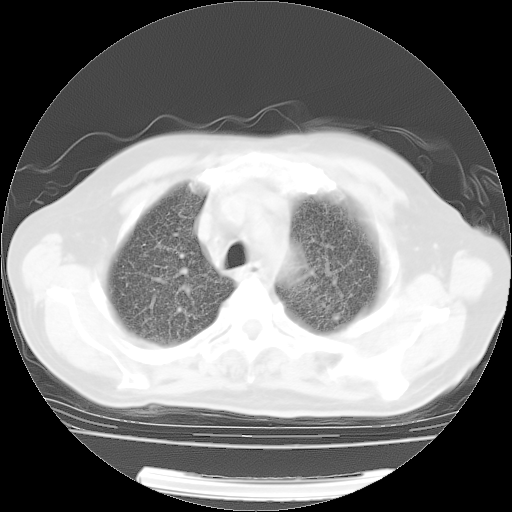

4月28日肺部CT——再次出现类似去年5月9日——透光度降低,(影像科认为)“间质性”改变。

4月28日肺部CT——再次出现类似去年5月9日——透光度降低,“间质性”改变。